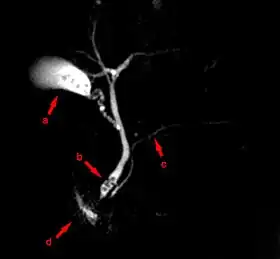

![]() MRCP image showing stones in the distal common bile duct: (a) Gallbladder with stones, (b) Stones in bile duct, (c) Pancreatic duct, (d) Duodenum. | |

Magnetic resonance cholangiopancreatography (MRCP) is a medical imaging technique. It uses magnetic resonance imaging to visualize the biliary and pancreatic ducts non-invasively. This procedure can be used to determine whether gallstones are lodged in any of the ducts surrounding the gallbladder.

MRCP is used to diagnose gallstones. It can also diagnose choledochal cysts very reliably.[5] Besides providing information regarding the biliary system, MRCP also provides information regarding surrounding solid organs and blood vessels, thus useful for planning the resection of pancreatic cancer and look for complications of primary sclerosing cholangitis such as liver cirrhosis and cholangiocarcinoma.[5]